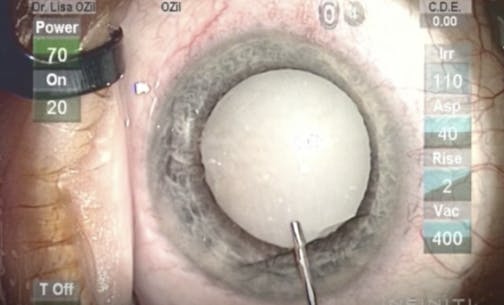

Unilateral Hypermature Tan Cataract

Lisa Brothers Arbisser, MD